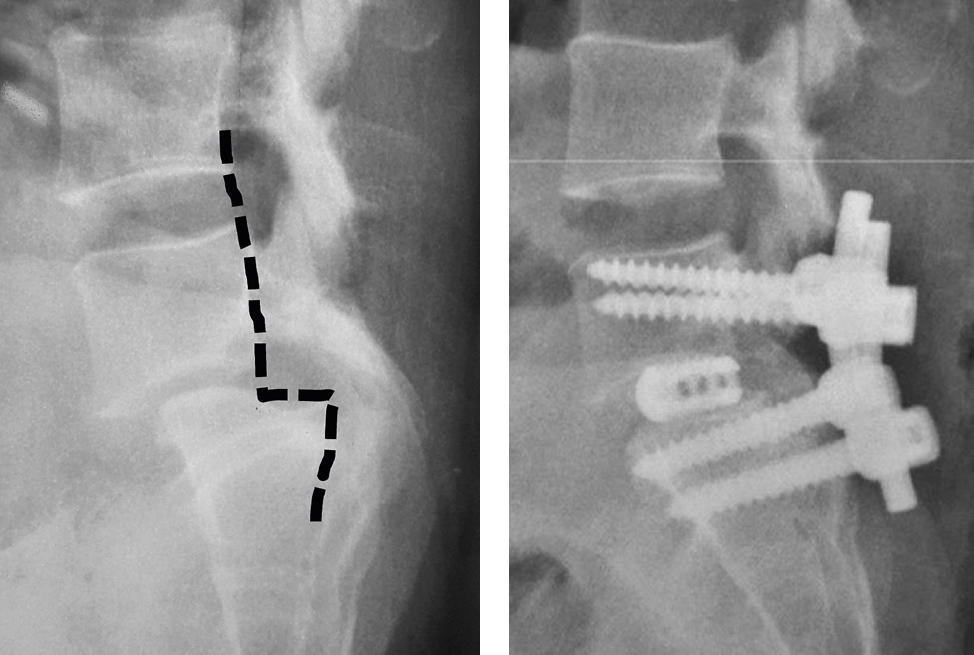

Case 2: Adult Spine Condition – When Stability Matters Most

A 29-year-old woman came with severe lower back pain and pain spreading to both legs. Walking had become difficult, and daily tasks were tiring.

Scans showed grade 3 spondylolisthesis, where one bone had slipped forward and disturbed spinal alignment.

Choosing the Right Surgical Method

In this situation, surgery was necessary. However, the method mattered greatly.

Dr. Yogesh K. Pithwa used a technique involving monoaxial screws, which help restore spinal balance and provide strong support. This approach allows better correction and long-term stability.

Such precision is often seen in experienced endoscopic spine surgeons in Bangalore, where careful planning leads to safer outcomes.

The Outcome

After surgery:

- Pain reduced significantly

- Walking became easier

- Posture improved

- Daily activities returned to normal

The spine remained stable even after recovery.